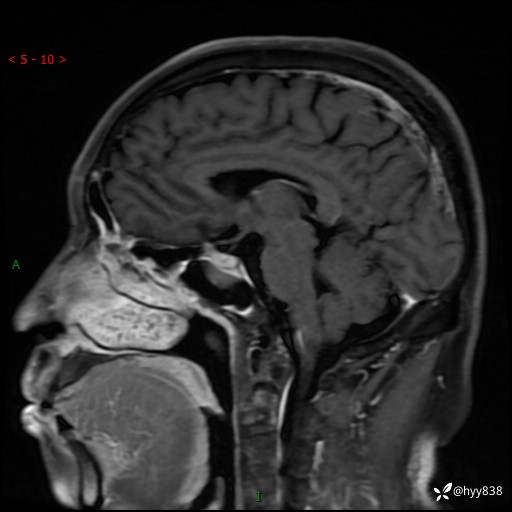

MRI增强(外院平扫)